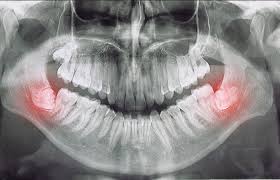

사랑니는 마지막 어금니로, 대부분 10대 후반~20대 초반에 올라오기 시작합니다. 문제는 이 치아가 제대로 자리를 잡지 못하고 옆 치아를 밀거나 잇몸 안쪽에 비스듬히 숨어 자라면서 통증과 염증을 일으킨다는 점입니다.

- 옆 치아 손상: 비스듬히 자란 사랑니가 인접한 어금니를 밀어 치아 뿌리 손상을 유발합니다.

- 잇몸 염증: 사랑니 주변에 음식물 찌꺼기가 쌓여 세균 번식이 생기며, 심하면 고름이 생길 수도 있습니다.

- 턱 통증 및 두통: 사랑니가 신경 근처에 닿을 경우, 턱관절 통증이나 두통으로 번질 수 있습니다.